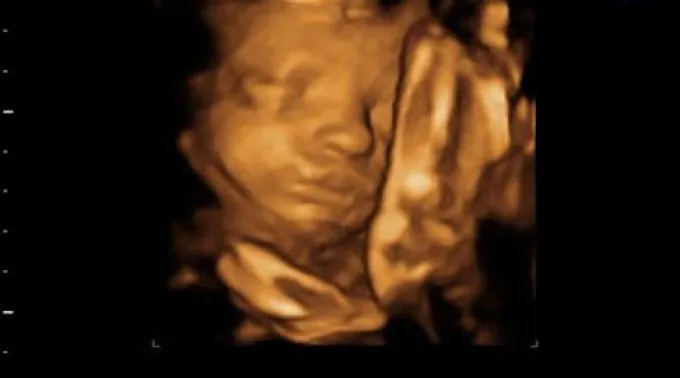

Os investigadores analisaram as seqüências de vídeo 4D de 15 fetos sãs (oito femininos e sete masculinos) de entre 24 a 36 semanas de gestação para examinar de perto todos os acontecimentos em um trecho de aftosa no feto e acharam que mais da metade das aberturas da boca observadas foram bocejos, conforme publica esta quarta-feira a prestigiosa revista científica 'Plos One'.

O bocejo reduziu a partir das 28 semanas e não houve diferenças significativas entre meninos e meninas na freqüência de bocejo.

"Nosso estudo longitudinal mostra que o bocejo diminui ao aumentar a idade fetal. A diferença de nós, os fetos não bocejam por contagio nem por sono, mas a freqüência dos bocejos no útero pode estar relacionado com o amadurecimento precoce do cérebro na gestação", disse Nadja Reissland, do Departamento da Universidade de Psicologia de Durham.

Assim, Reissland concretizou que tendo em conta que a freqüência de bocejos na mostra de fetos sãos reduziu a partir das 28 semanas até as 36 semanas de gestação, parece que o bocejo e a abertura bocal poderiam estar relacionados com o amadurecimento durante a gestação, por exemplo, do sistema nervoso central.